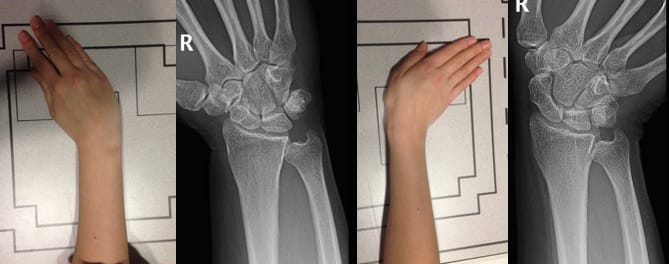

The standard frontal and lateral projections required to achieve good visualisation of the joint have been thoroughly described by Kapandji [9], Kapandji AI, Moatti E, Raab C. La radiographie spécifique de l’articulation trapézo-métacarpienne. Sa technique, son intérêt. Ann Chir Main 1980;34:719-26.[10] Kapandji TG, Kapandji AI. Nouvelles données radiologique sur la trapézo-métacarpienne. Résultats sur 330 dossiers. Ann Chir Main 1993, 12 , N°4, 263-274 and these are still an excellent reference. A posteroanterior projection (Figure 1) is used for the frontal view otherwise the metacarpophalangeal and interphalangeal joints would be visualised first (Figure 1). The lateral view is achieved through an ulnar to radial projection (Figure 2). Across the Atlantic, variations to these projections exist and some useful additions are made. Robert’s view [11] Robert P. La radiographie de l’articulation trapézo-métacarpienne. Les arthroses de cette jointure. Bulletins et mémoires de la Société de Radiologie Médicale de France. 1936;24:687-90. is a variant of the Kapandji frontal view that uses an AP rather than PA projection and is very popular in the English-speaking world. We should not forget comparative images, such as the Eaton view with and without stress. To assess the triscaphoid it is important to include Gedda’s view [12] Gedda KO (1954). Studies on Bennett’s fracture: anatomy, roentgenology and therapy. Acta Chirurgica Scandinavica, 193(Suppl): 1. , also known as Bett’s view [13] Taleisnik J. The Wrist, 1st edn. New York, Churchill Livingstone, 1985: 95–96. , among dynamic views in ulnar and radial deviation. We will move on to a detailed discussion of the key views and their positioning.

Frontal views : This radiography is performed using dorsopalmar and lateral projections. For the frontal view it is crucial for the sesamoids to project over the first metacarpal head. (Figure 1). These frontal images clearly show the IP and thumb MCP joint spaces. The TMC joint space, however, cannot be visualised simultaneously.

Lateral views : These are carried out in the exact same way as Kapandji’s lateral views: it is key to make sure the sesamoids are superimposed on lateral views as this will demonstrate the concave base of the first metacarpal and the convexity of the trapezium while enabling the base of the second metacarpal to be slightly superimposed. (Figure 2) This view allows for a very good appreciation of the involvement of the MCP and IP joints.

Kapandji’s frontal view equates to the Eaton view without stress, and involves placing the thumb in extension while moving the wrist into slight ulnar deviation (Figure 3). This offers good visualisation of the trapeziometacarpal joint.